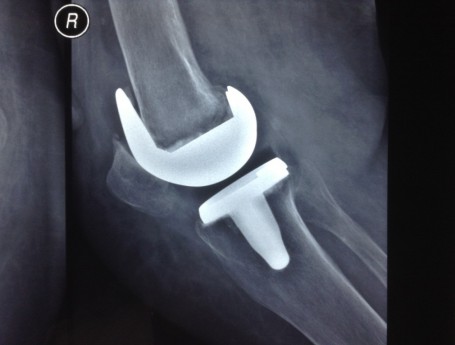

Revision Total Knee Replacement After a fructure

• Revision Total Knee Replacement After a fructure